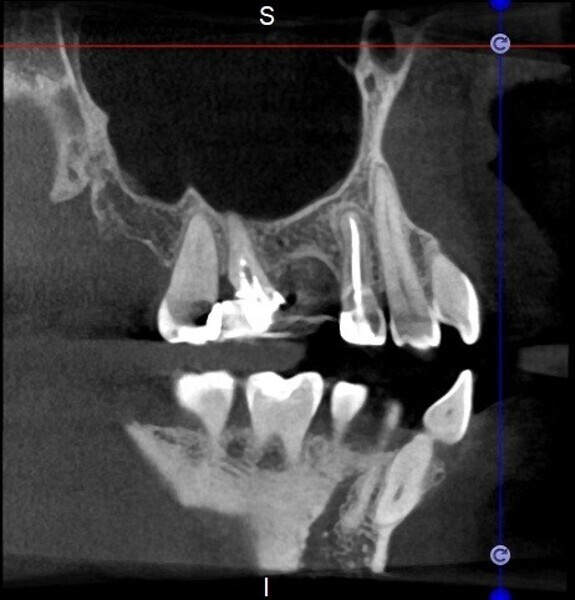

Use of 3D technology in the diagnosis and treatment of endodontic disease